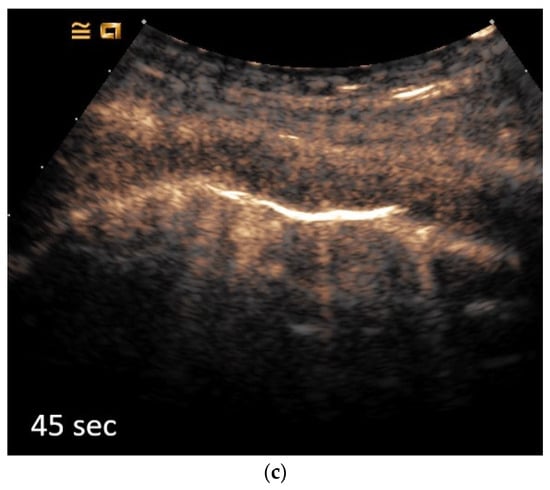

Contrast-Enhanced Ultrasound (CEUS) of the Lung and Pleura

2. Primary Pulmonary Sarcomas